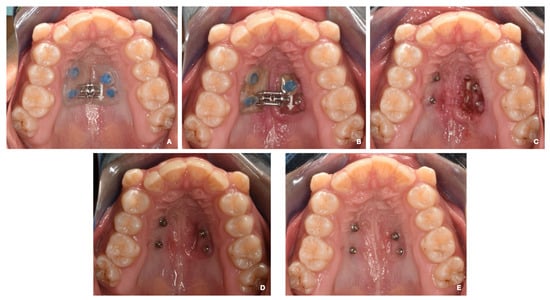

2. Case Report